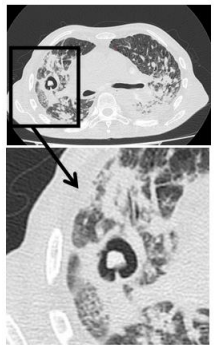

A seguir, está a imagem da tomografia computadorizada realizada.

O laudo da tomografia computadorizada do tórax foi: derrame pleural laminar bilateralmente. Sinais de enfisema centrolobular Cavitações de paredes espessadas no pulmão direito, uma delas apresentando formação nodular com densidade de partes moles no seu interior, medindo cerca de 1,1 x 0,9 cm, de aspecto pouco específico. Múltiplas opacidades centrolobulares esparsas por ambos os pulmões, assumindo configuração com aspecto de árvore em brotamento bilateralmente, associados a opacidades em vidro fosco na sua adjacência. Dentre os diagnósticos diferenciais deve-se considerar a possibilidade de processo infeccioso específico em atividade Espessamento difuso das paredes brônquicas. Traqueia e brônquios-fonte pérvios. Linfonodos proeminentes mediastinais e hilares, muitos calcificados. Aorta de calibre preservado. Calcificações vasculares. Coração de dimensões aumentadas.

A seguir, está a imagem da tomografia computadorizada realizada.

O laudo da tomografia computadorizada do tórax foi: derrame pleural laminar bilateralmente. Sinais de enfisema centrolobular Cavitações de paredes espessadas no pulmão direito, uma delas apresentando formação nodular com densidade de partes moles no seu interior, medindo cerca de 1,1 x 0,9 cm, de aspecto pouco específico. Múltiplas opacidades centrolobulares esparsas por ambos os pulmões, assumindo configuração com aspecto de árvore em brotamento bilateralmente, associados a opacidades em vidro fosco na sua adjacência. Dentre os diagnósticos diferenciais deve-se considerar a possibilidade de processo infeccioso específico em atividade Espessamento difuso das paredes brônquicas. Traqueia e brônquios-fonte pérvios. Linfonodos proeminentes mediastinais e hilares, muitos calcificados. Aorta de calibre preservado. Calcificações vasculares. Coração de dimensões aumentadas.